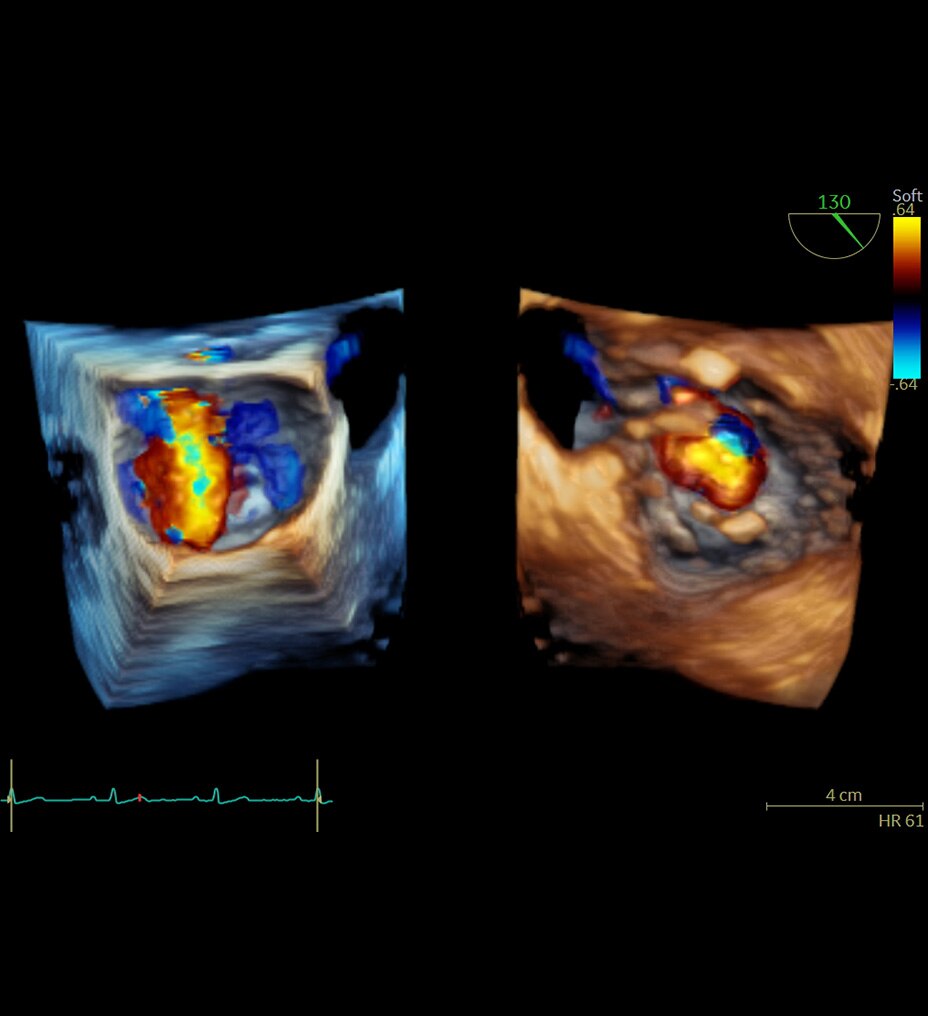

POWER DOPPLER IMAGING

Visualize slower blood flows

Power Doppler Imaging + (PDI+) is a color flow mapping technique used to map the strength of a Doppler signal coming from the flow rather than the frequency shift of the signal. In PDI+ mode, the sensitivity of the color in the Region of Interest (ROI) increases. Providing a higher resolution than the regular PDI mode, PDI+ is best used for slower blood flows such as those found in wrists, ankles, hands, and feet. This is an additional option that exists within the regular PDI mode.